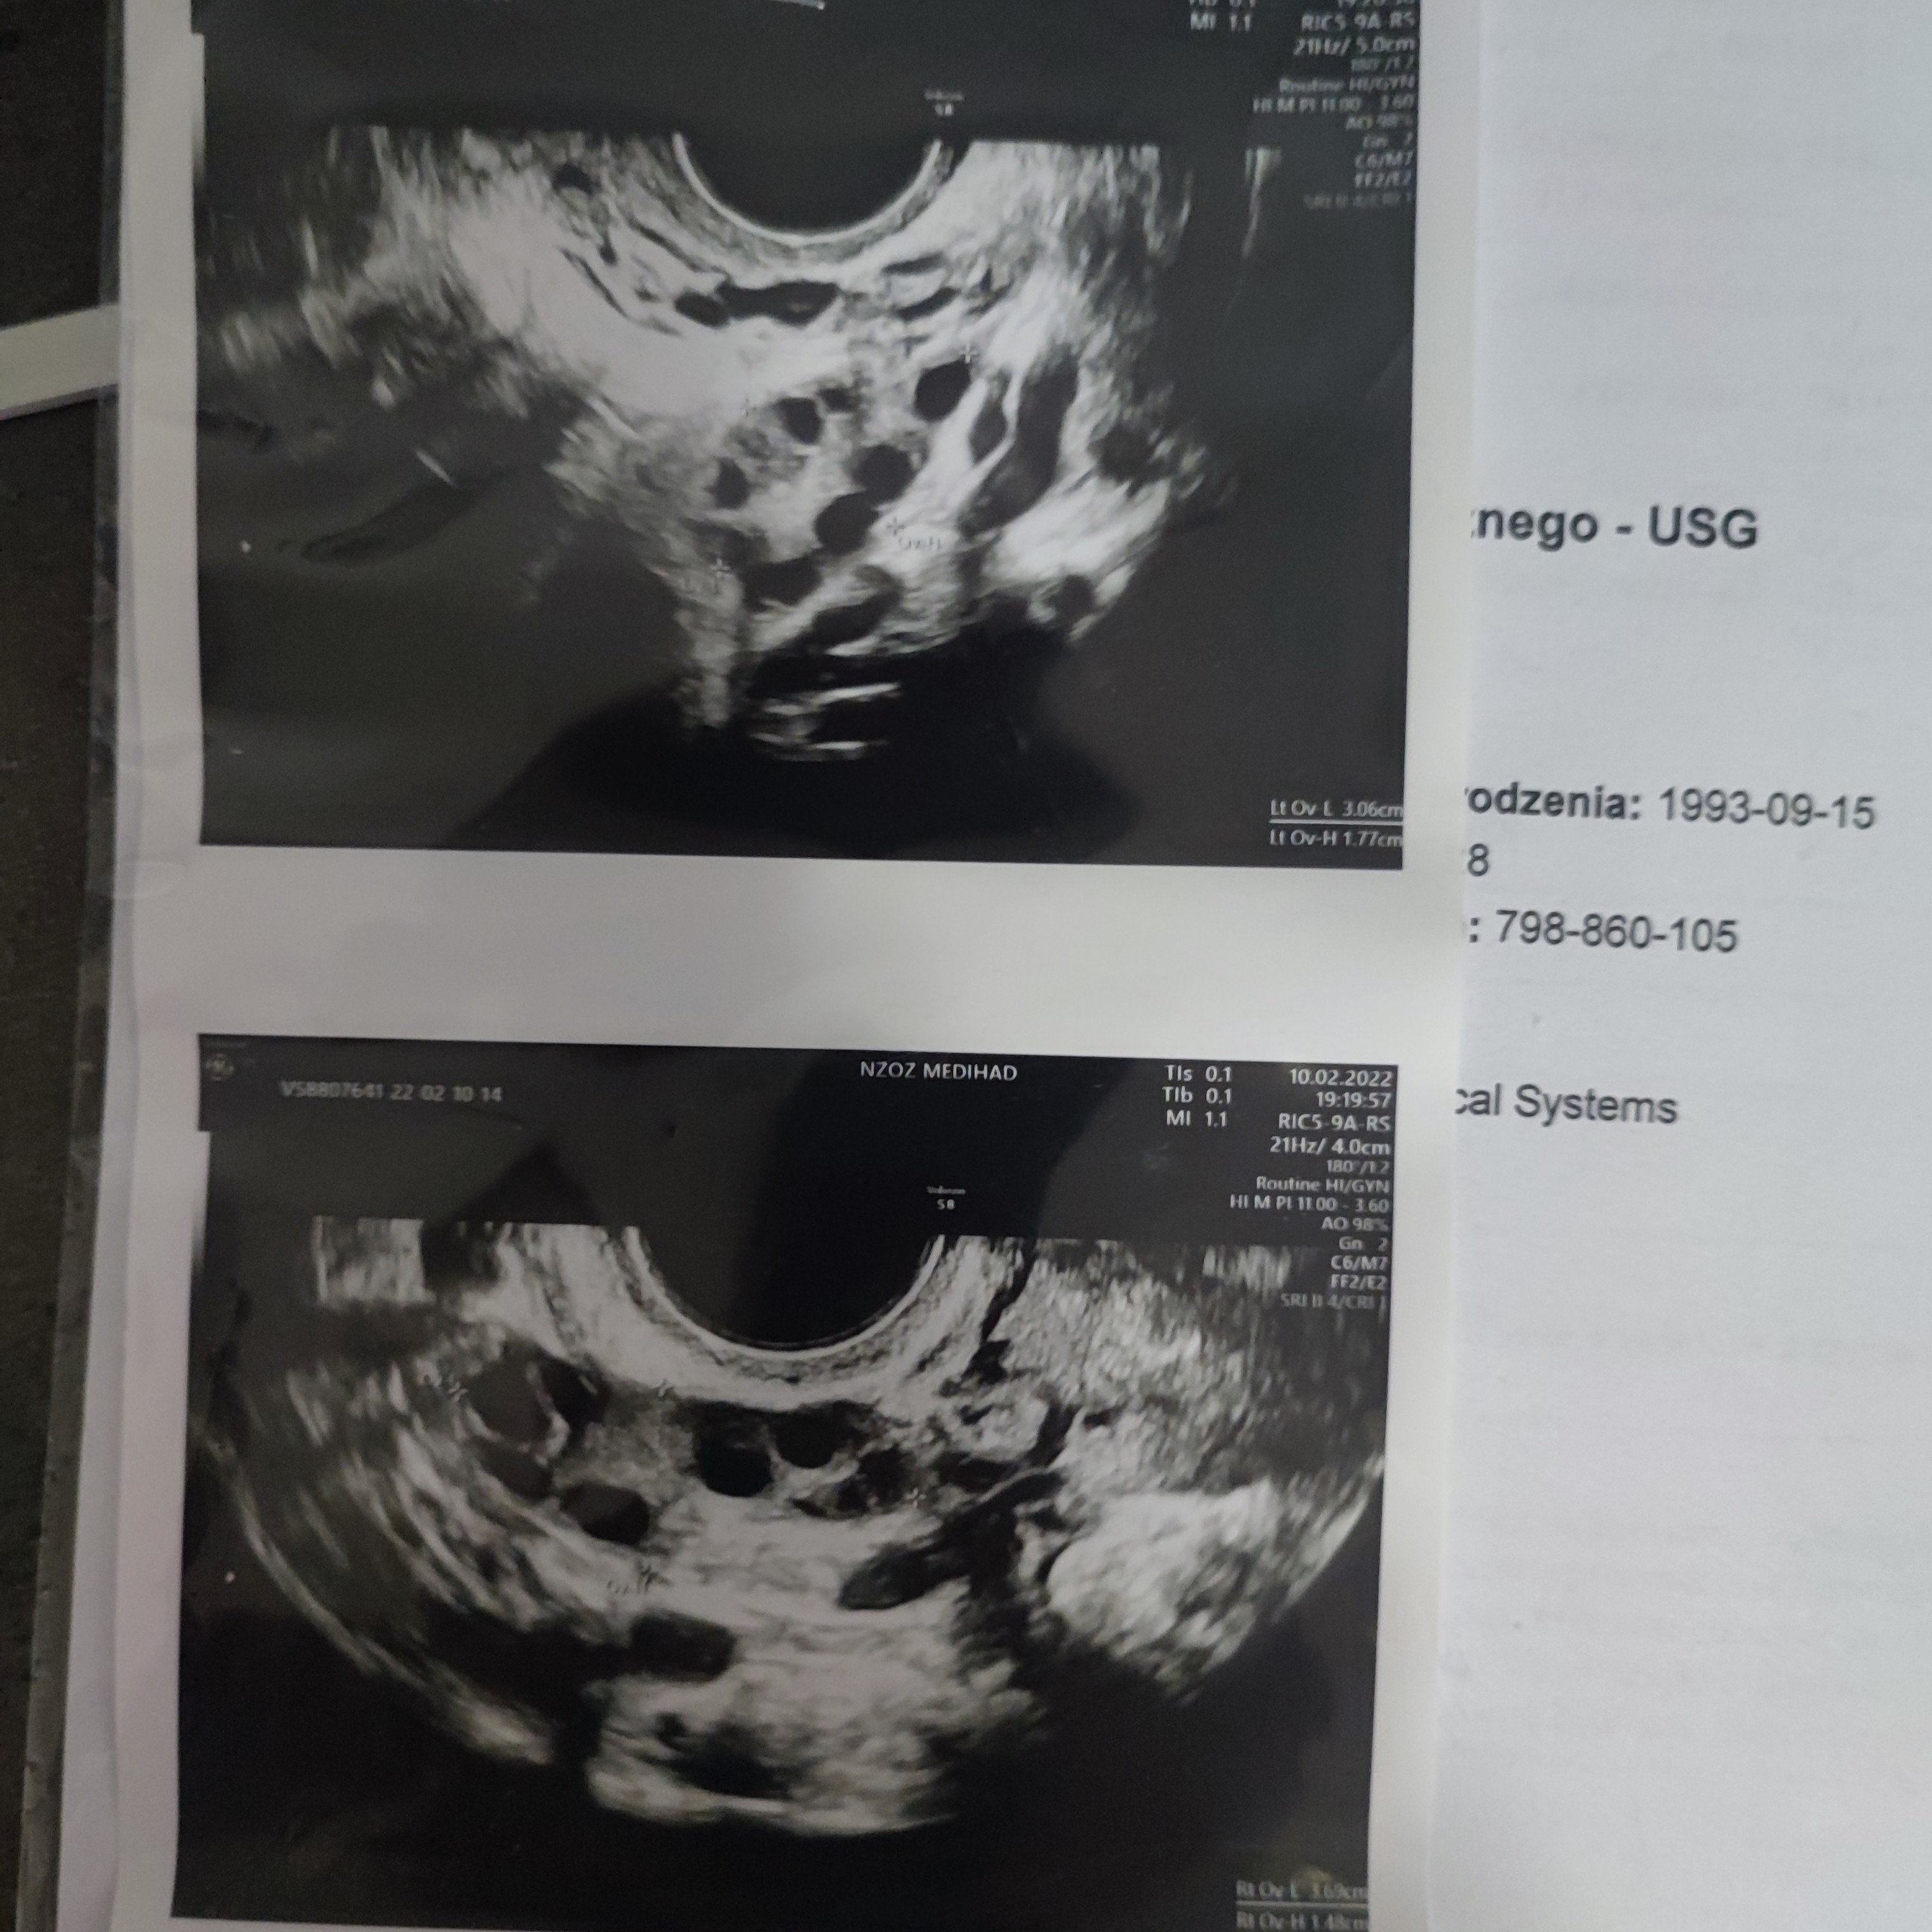

Tak wyglądają obecnie moje jajniki, niby jakieś pęcherzyki są, ale nie pękają. AMH mam 8.8, to chyba jakieś mam 🙈 Nie wiem jak mam interpretować to zdj USG. Kurde nic już nie wiem 😂

Znam się mało, no ale jak wysokie AMH, dużo niepękających pęcherzyków to PCOS? Badałaś LH i FSH?

No właśnie jak o to ostatnio zapytałam, to powiedziała, że nie wygląda to na PCOS... jak dla mnie to jest właśnie to, ale lekarzem nie jestem. Mam już córkę, która w tym roku skończy 11 lat, więc musiało się ze mną coś porobić z wiekiem. Stara aż taka nie jestem, bo w tym roku będę mieć 29 lat. Jak byłam na pierwszej wizycie u gina jak zaszłam w ciążę (18 lat), to powiedział, żebym się nie denerwowała, bo najlepszy wiek do zachodzenia w ciążę dla kobiet to 18-25 lat 😂 a potem różnie bywa... No wykrakał mi 😐